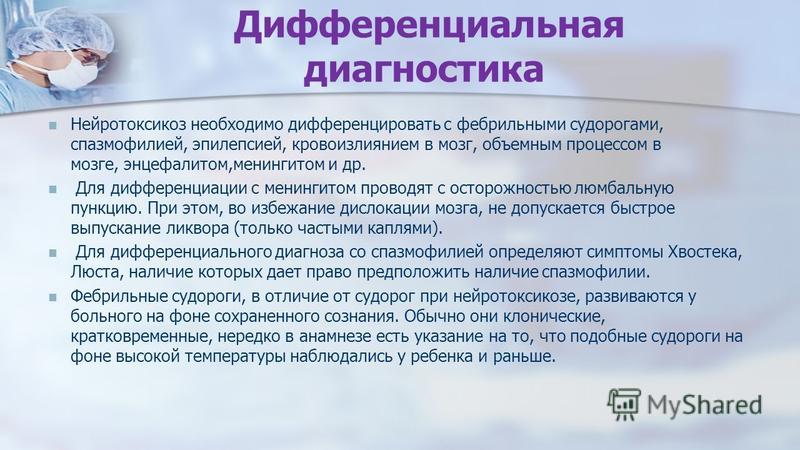

Дифференциальная диагностика заболеваний плевры